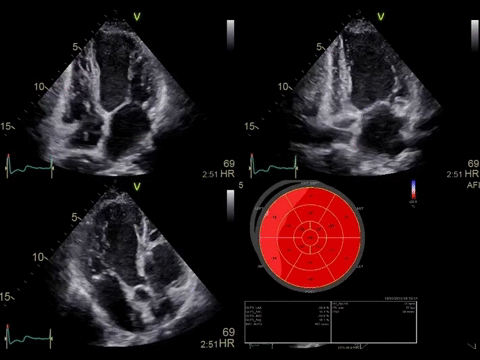

УЗИ аппарат Vivid E95 – это система 4D-сканирования премиум-класса, разработанная инженерами GE для наиболее сложных задач в области комплексной диагностической медицины. Синергия стационарной платформы Vivid и инновационной технологии cSound формирования ультразвукового луча позволяют добиваться потрясающих результатов в области сердечно-сосудистых исследований пациентов.

В сравнении с обычными УЗИ-станциями, Vivid E95 – это настоящая машина по агрегированию гораздо большего количества данных, используя технологии точной конфокальной визуализации (TCI) и адаптивного контрастного усиления (ACE). Изображения снимков, которые способен выдавать этот аппарат, поражают воображения. Забудьте о «зерне» на записях.

Vivid E95 – это интеллектуальная система, способная проводить различного рода обследования, благодаря усовершенствованным двухмерным и цветовым доплеровским изображениям. Теперь время, проведенное с пациентом, становится бесценным. Ведь количество неинформативных исследований снижается.

• Автоматическая оценка регионарной сократимости миокарда левого желудочка с расчетом большой группы параметров с помощью функции Automated Function Imaging (AFI).

• Протоколы AFI Stress, позволяющие получать стандартные апикальные проекции в двумерном режиме и рассчитывать регионарную и глобальную продольную деформацию миокарда на всех уровнях нагрузки.

• Функция 4D Strain для расчета глобальной и регионарной деформации миокарда на основе алгоритма пространственного спекл-трекинга, отображаемая в виде диаграммы «бычий глаз».